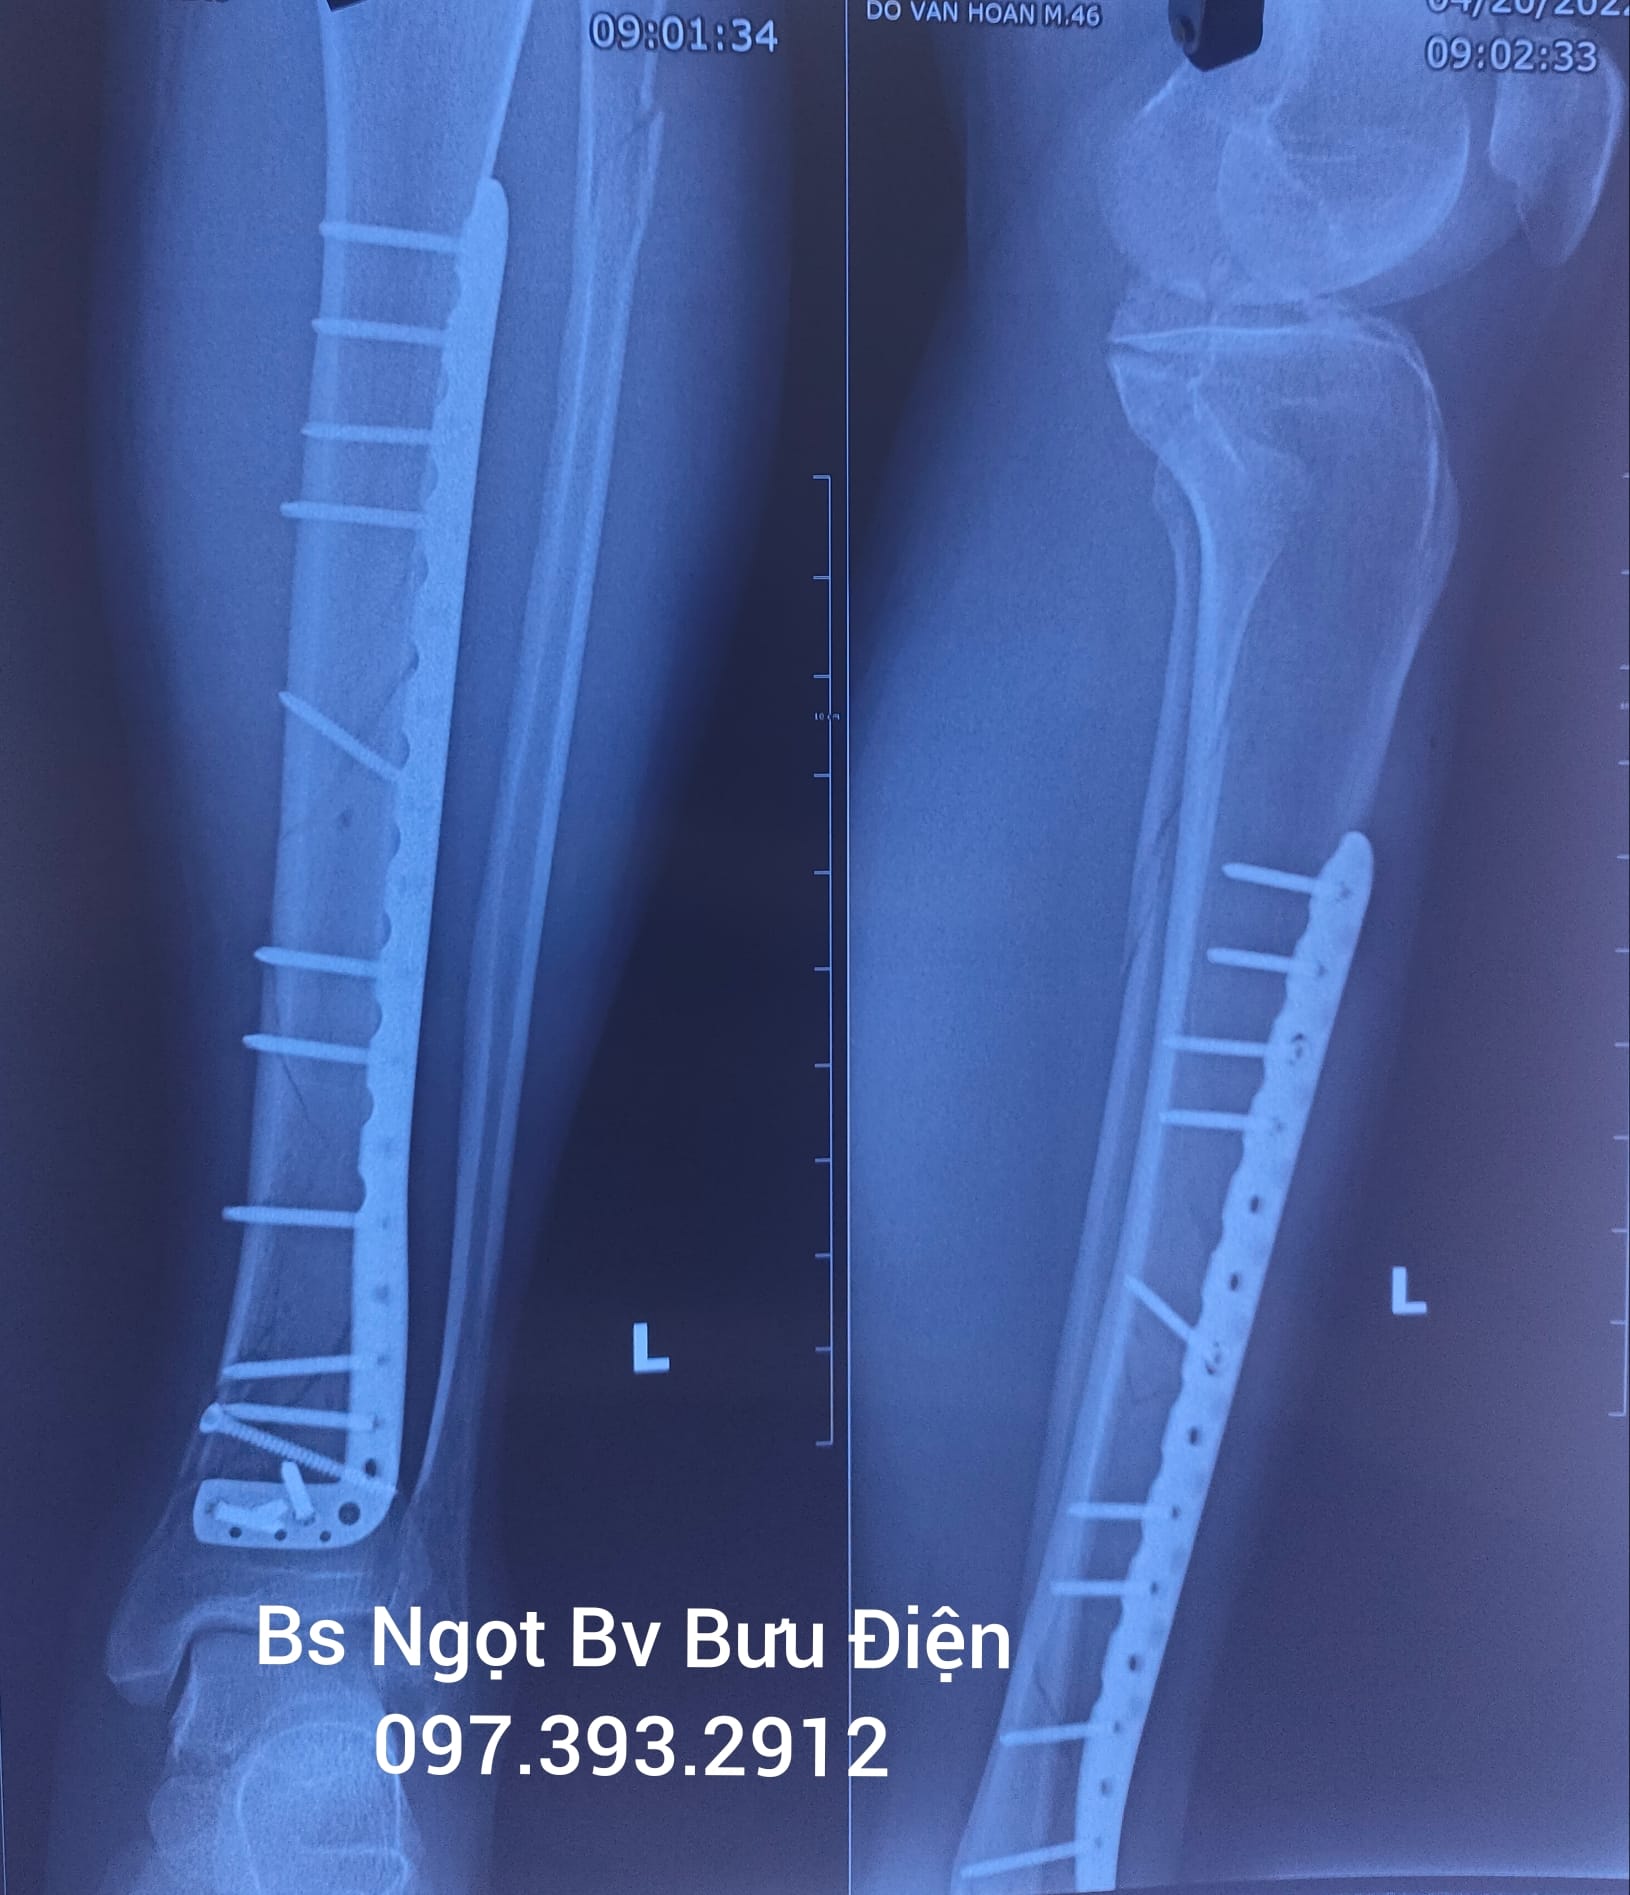

Phẫu thuật kết hợp xương chày bằng nẹp vis

Gãy thân xương chày hay gãy xương chày là sự gián đoạn cấu trúc toàn vẹn của xương chày do chấn thương trực tiếp hoặc gián tiếp gây đau và hạn chế vận động khớp gối và khớp cổ chân. Gãy thân xương chày ảnh hưởng nặng nề tới...